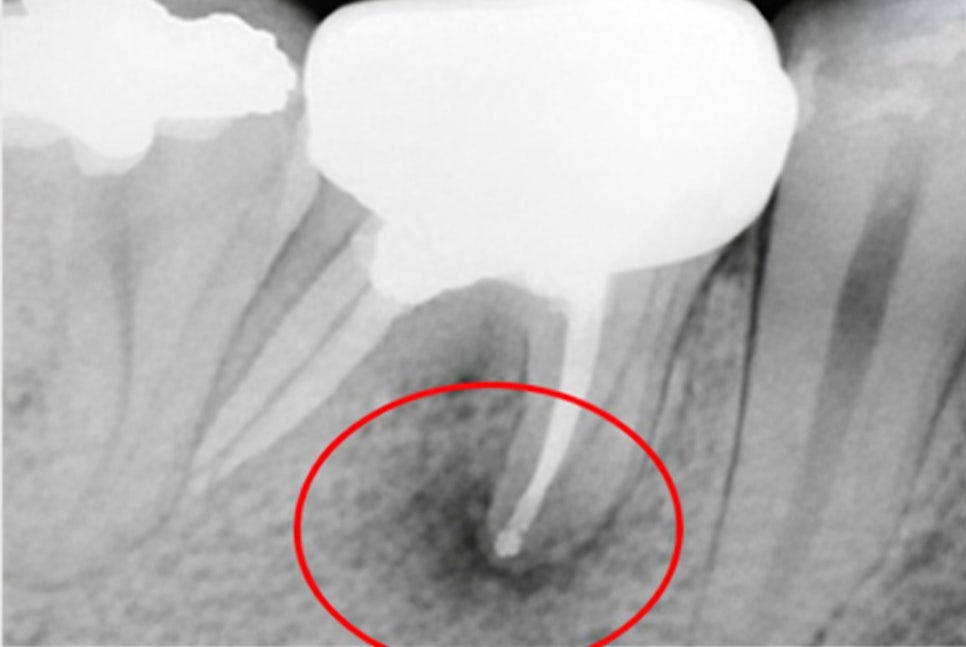

특히 크라운을 씌운 곳은

보철을 제거하기 전까지

정확한 상태를 확인하기 어려우며

이미 근관이 충전되어 있다면

잇몸에 염증이 생기면서

알게 될 때가 많습니다.

2차 우식은 크라운 아래에서 진행되기 때문에

초기에는 겉으로 드러나는 변화가 없을 수 있습니다.

또한 보철 아래에서 발생한 충치는

외부 공기와 접촉하지 않기 때문에

비교적 습하고 밀폐된 환경에서

빠르게 진행될 수 있습니다.

그 결과 치질이 약해지고

결국 치수까지 감염되거나

치근단 염증으로 이어질 수 있으며

재수복만으로는 해결이 어려워집니다.